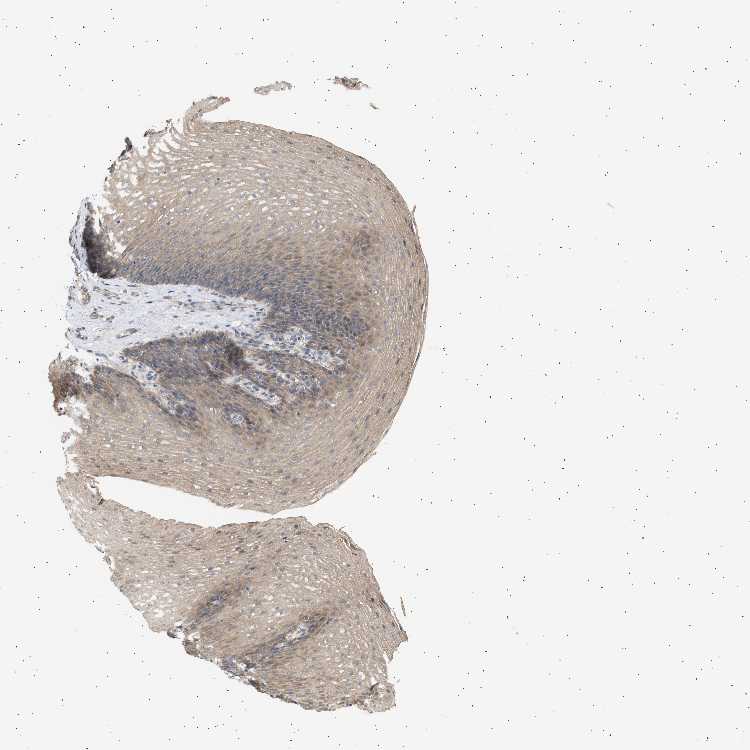

ESOPHAGUS - Antibody stainingi

Antibody staining in the annotated cell types in the current human tissue is reported as not detected, low, medium, or high, based on conventional immunohistochemistry profiling in selected tissues. This score is based on the combination of the staining intensity and fraction of stained cells.

Each image is clickable and will lead to virtual microscopy that enables deeper exploration of all samples and also displays staining intensity scores, fraction scores and subcellular localization as well as patient and tissue information for each sample.

Antibody CAB016944

Squamous epithelial cells Medium